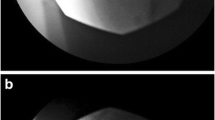

Waleed Haddad et al. [69] applied a retrograde technique to access the S2–S4 sacral canal (Fig. 1). The patient experienced more than 95% pain relief during the 6-day trial period and as a result the permanent implantable neurostimulator was performed. The patient was comfortable with the SCS setting of frequency 50 Hz, and pulse width range of 300–350 µs.

Lateral view of lead placement (S2–S4 level), from Waleed Haddad et al. [69]